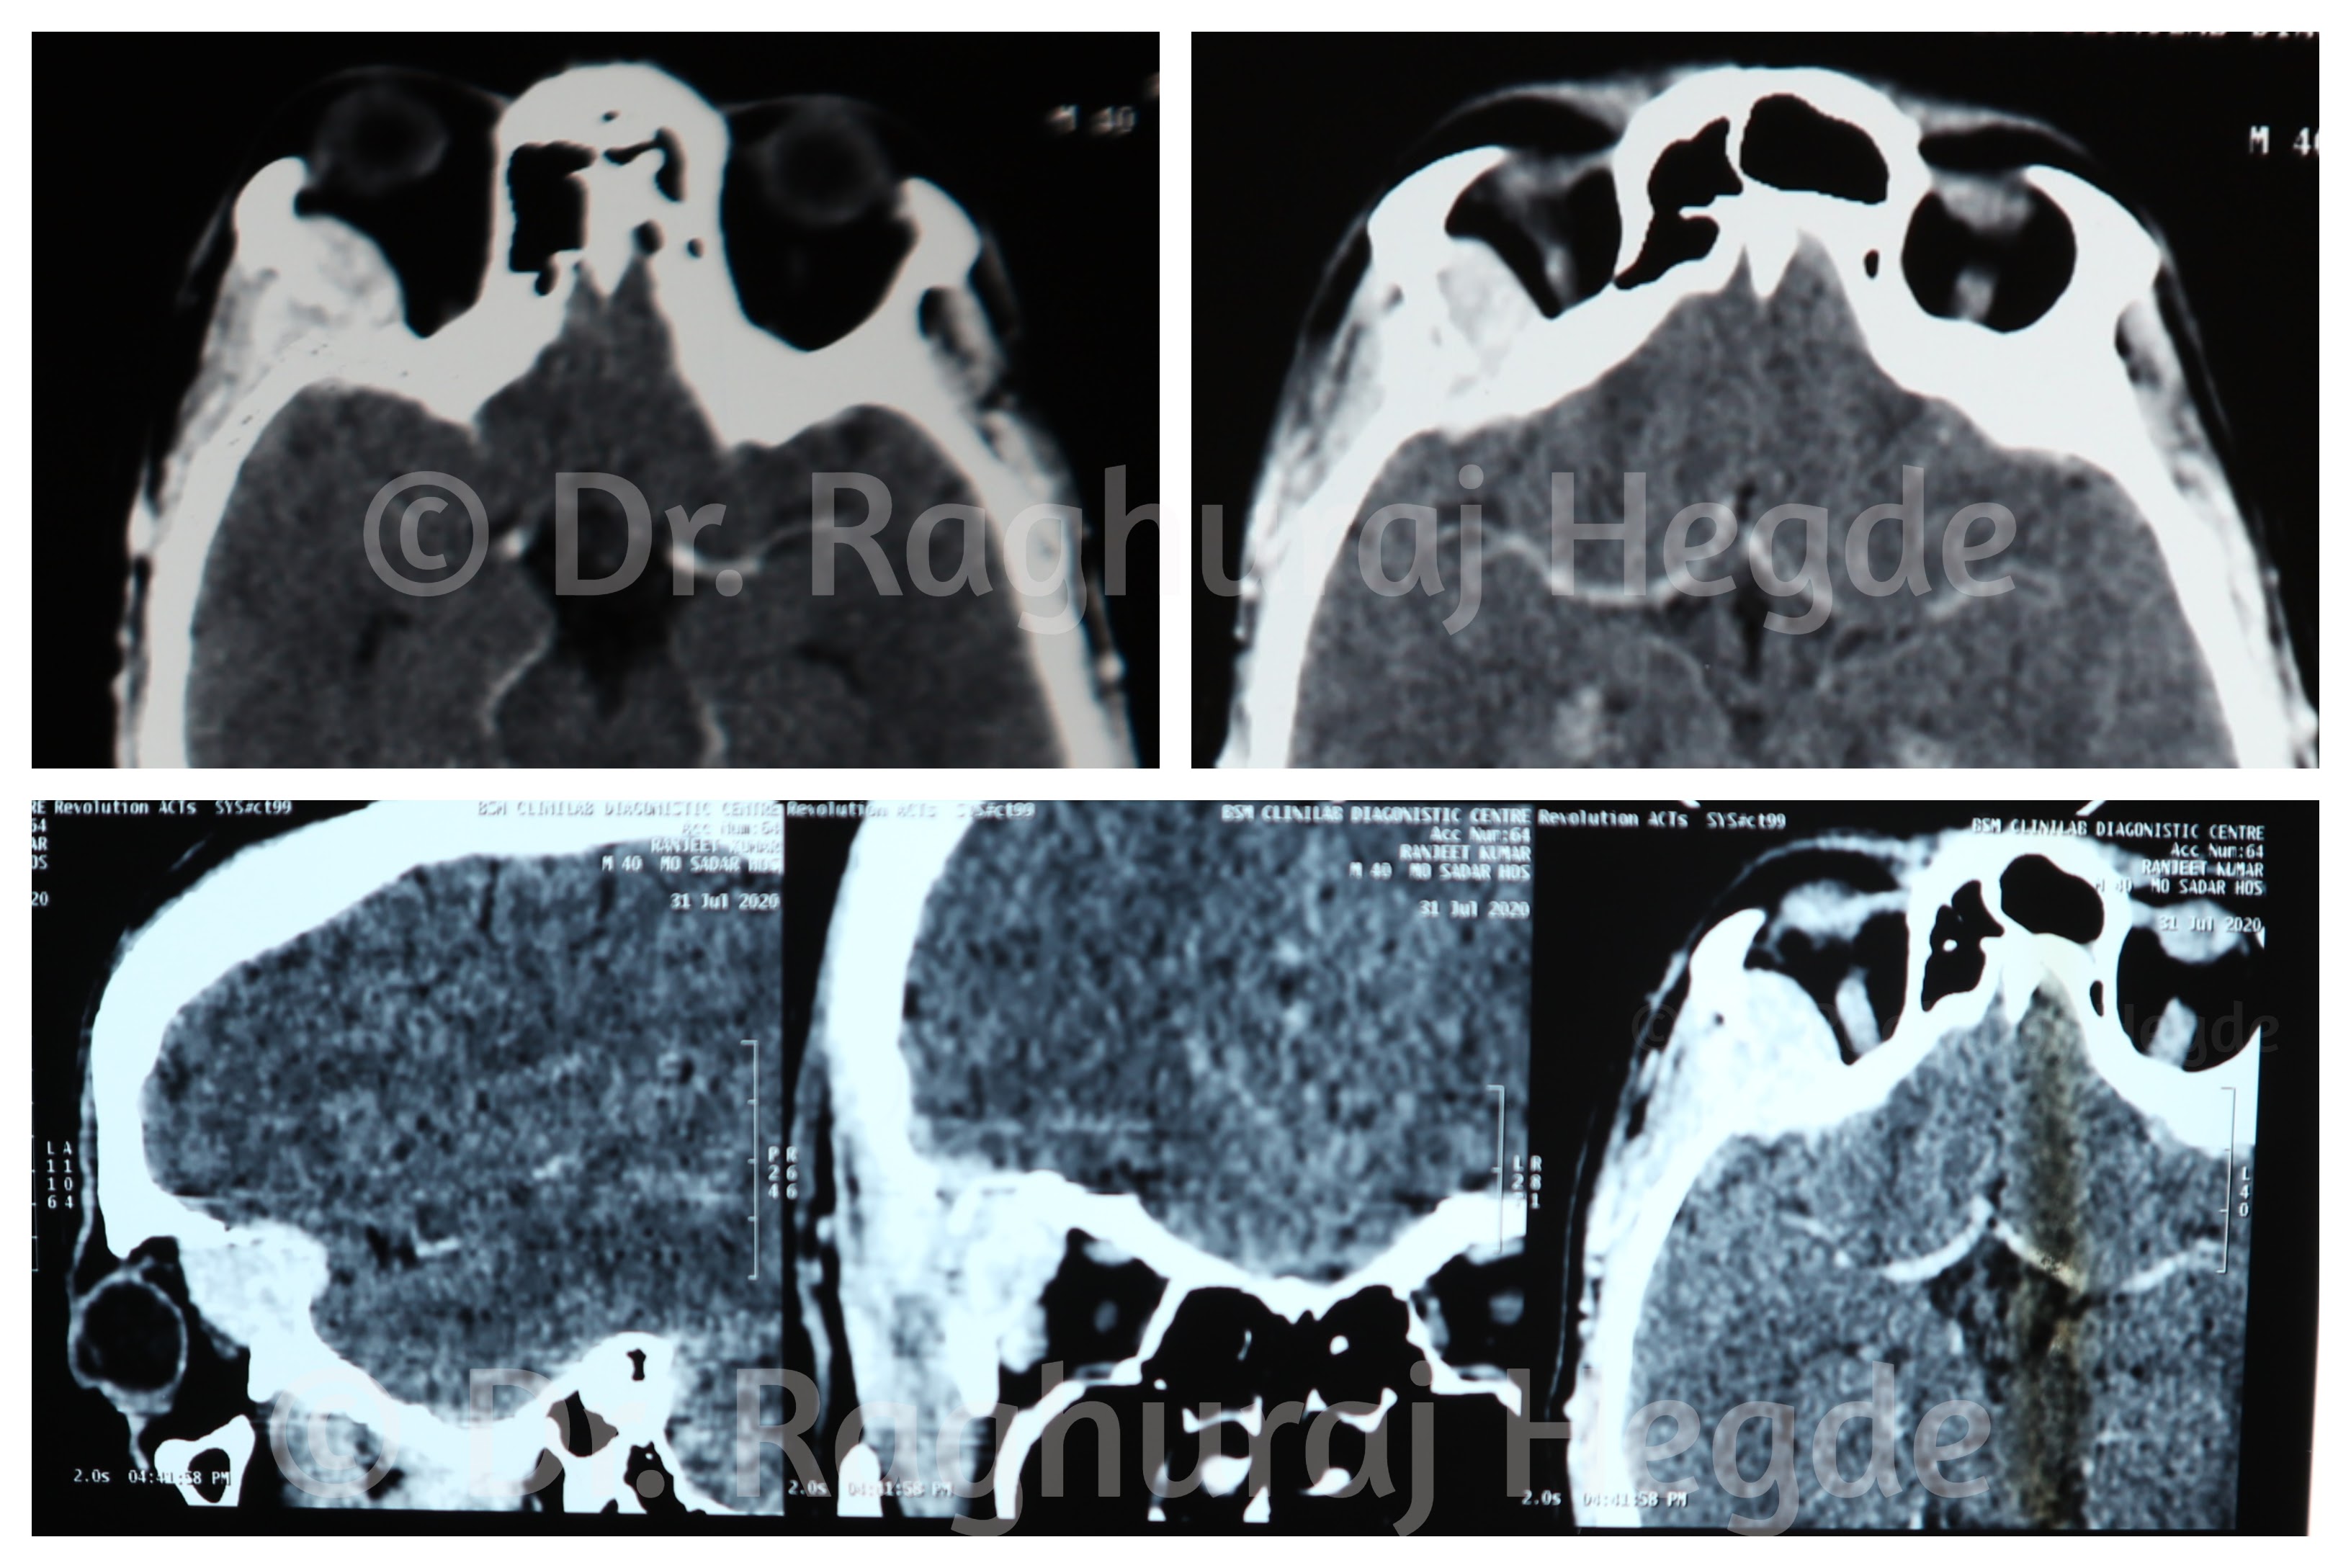

This below are the CT and MRI collages showing the tumour occupying the supero-lateral part of the right orbit causing lytic bone destruction of the lateral orbital wall up to the lateral skull base. It is present in the extra-conal space of the orbit extending to the epidural space and infiltrating the right temporalis muscle. It is important to note here that there is no infiltration into the peri-orbita as well as the dura. This was confirmed intra-operatively.